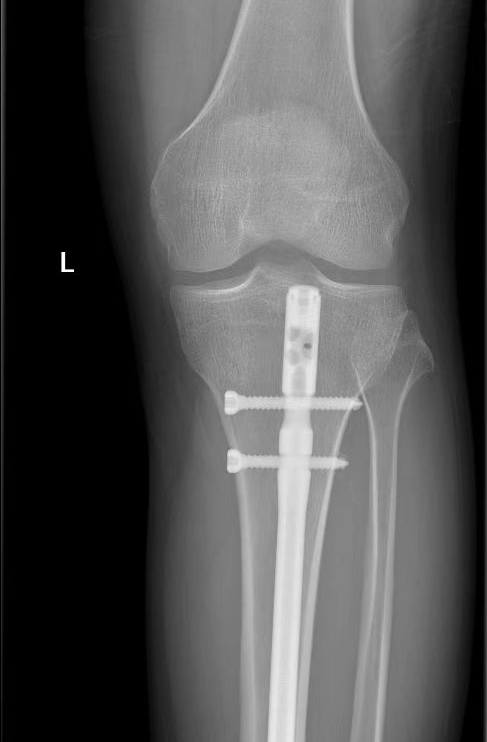

患者左胫骨骨折手术同样采用微创经皮髓内钉固定的方法,这种术式减轻了患者创伤,但对术者的技术要求较高。李清主任从患者胫骨上端切开一个小切口,小心翼翼地把髓内钉置入胫骨内,复位固定胫骨,C 臂机透视证实,骨折对位对线良好,内固定物位置适当,手术成功。